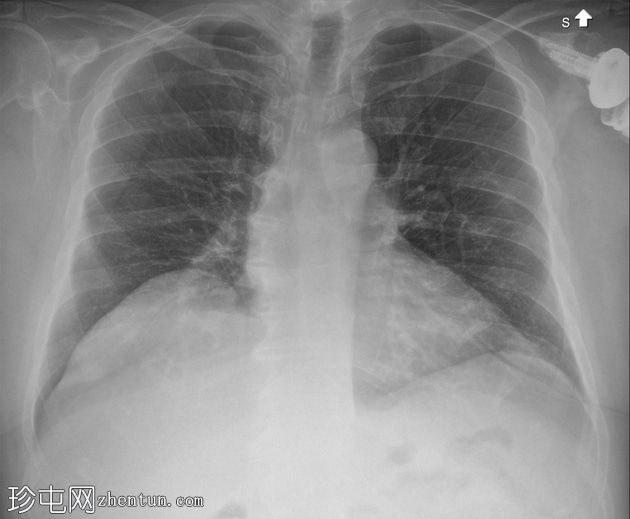

胸部

X光片

1.jpg

正面